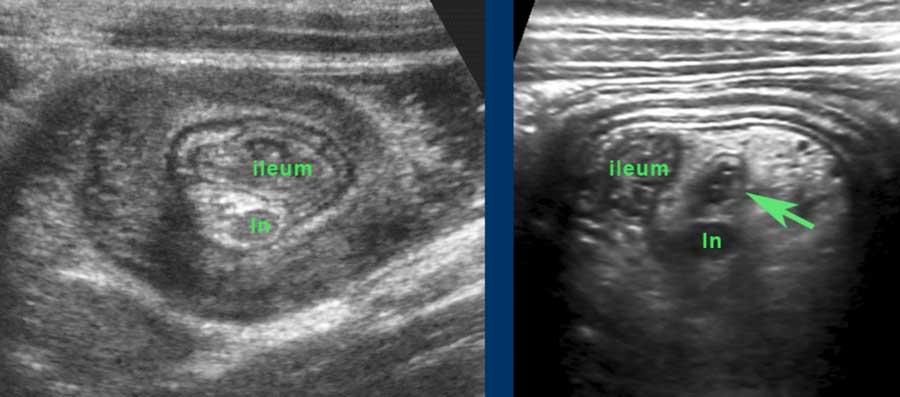

Hình ảnh siêu âm kinh điển của lồng ruột hồi-manh tràng ở hai trẻ khác nhau.

Trong cả hai trường hợp, đoạn hồi tràng bị lồng được định vị không đối xứng bên trong ống lồng ngoài, do mạc treo ruột tăng âm có chứa mỡ, bám vào hồi tràng và đi theo hồi tràng khi bị kéo vào trong.

Trong mạc treo, siêu âm cho thấy một hạch bạch huyết mạc treo (hbh) phóng đại ở cả hai.

Các hạch này phì đại như một phần của tình trạng tăng sản hạch bạch huyết toàn thân và khônghu trú trong lòng hồi tràng.

Do đó đây không phải là điểm dẫn đầu nguyên phát. Ở bệnh nhân bên phải, ruột thừa (mũi tên) cũng bị kéo vào trong.

Lưu ý cấu trúc đa lớp của thành bụng phía trước của phức hợp lồng ruột, đại diện cho ba lớp thành ruột bị gấp lại.